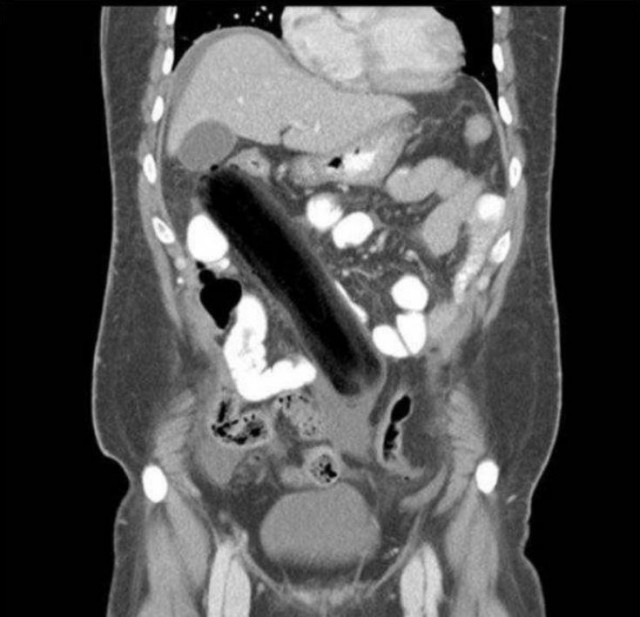

・もう手術でもしないと取り出せないような位置に!